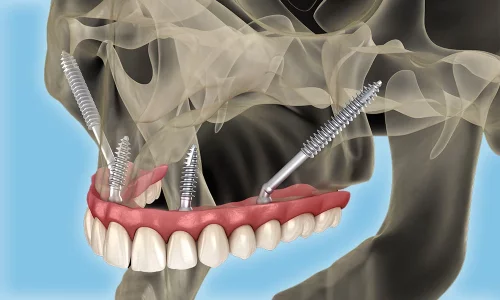

Pour de nombreux patients souffrant d'une perte osseuse sévère de la mâchoire supérieure, les implants dentaires traditionnels ne sont plus une option viable. Des années de perte de dents, des maladies parodontales ou des implants précédemment échoués peuvent résulter en une détérioration osseuse telle que les solutions conventionnelles ne fonctionnent tout simplement pas. C'est là que les implants zygomatiques interviennent — et chez Milim Dental, nous sommes spécialisés dans la délivrance de résultats réussis même pour les cas les plus défiants.

Découvrez comment les implants zygomatiques restaurent les dents en cas de perte osseuse importante de la mâchoire supérieure.